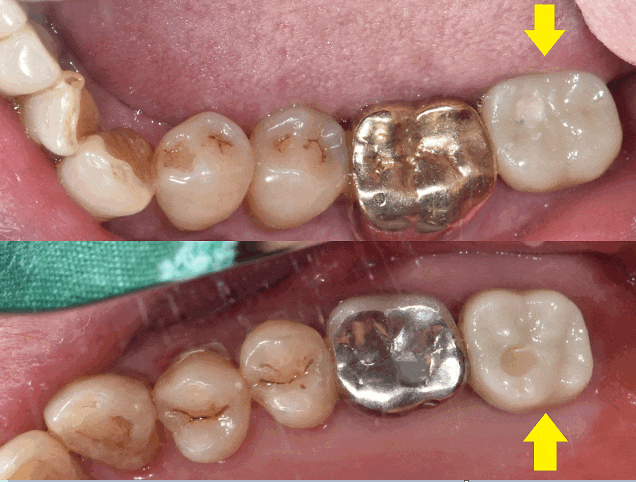

오른쪽은 치아 개수가 모두 있는 환자분

왼쪽은 위 아래 어금니 1개씩 사이좋게 없었습니다.

230622